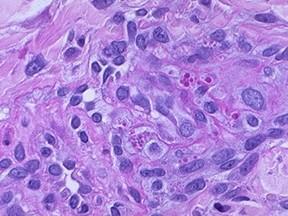

3.組織病理 :表皮內或表皮下可見水皰或膿皰,有網狀變性和氣球變性,常有多核上皮細胞,真皮有大量炎細胞浸潤,以中性白細胞為主,基底層細胞原漿內有Guarnieri小體(牛痘病毒包涵體)。